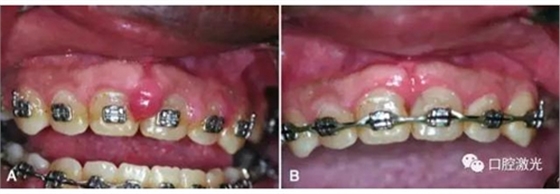

激光牙齦切除術(shù)治療牙齦增生

A:手術(shù)前,B:手術(shù)后10天效果